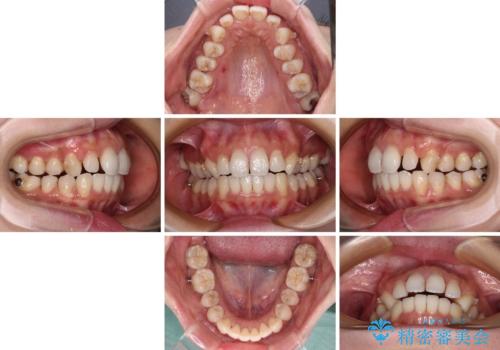

歯列としてはインビザラインでもワイヤー矯正でも対応できるものでしたが、奥歯の咬み合わせを見た時に上顎がやや前方にあり、インビザライン単独では時間のかかってしまう可能性があるため、補助装置を治療当初に使用することで、インビザラインによる治療をスムーズに行えるように計画しました。

インビザラインは得意・不得意の差がはっきりとしているため、補助装置やワイヤー装置などをうまく活用することで、治療期間を短縮するとともに、より理想的な仕上がりを達成することができます。